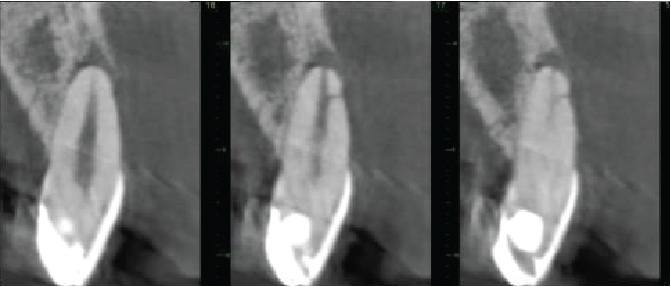

Cross sectional images of UR1

Mesio-distal

Labio-palatal

Cross sectional images of UL1

The UR1 is heavily restored. The root canal is patent, with a lateral canal directed mesiolabially 3mm from the root apex. A periapical granuloma is extending down the mesial and labial sides of the root, with a fenestration of the labial cortical plate. There is apical inflammatory root resorption.

The UL1 has a very similar appearance to the UR1. The root canal is patent, with a lateral canal directed labially 2mm from the root apex. A periapical granuloma is extending down the labial side of the root, with a large fenestration of the labial cortical plate. There is apical inflammatory root resorption.